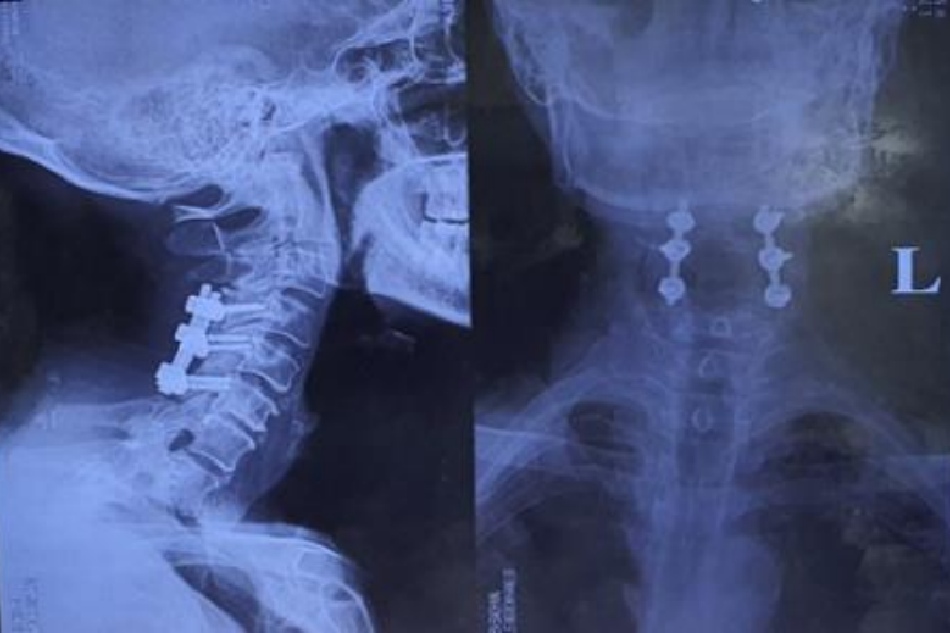

Bài viết ĐÁNH GIÁ KẾT QUẢ PHẪU THUẬT VÍT QUA KHỚP ĐIỀU TRỊ CHẤN THƯƠNG MẤT VỮNG C1-C2 THEO DÕI SAU 10 NĂM – Tải file PDF Tại đây. Tác giả: Hoàng Gia Du*, Lê Đăng Tân* TÓM TẮT Mục tiêu: Đánh gía kết quả điều trị xa các bệnh nhân (BN) chấn thương mất… Xem thêm

Bài viết ĐỘ CHÍNH XÁC VÍT QUA KHỚP ĐIỂU TRỊ MẤT VỮNG C1 – C2: BÁO CÁO 52 TRƯỜNG HỢP – tải file PDF Tại đây. Tác giả: Hoàng Gia Du, Vũ Xuân Phước – Khoa Chấn thương chỉnh hình và Cột sống, Bệnh viện Bạch Mai TÓM TẮT Đặt vấn để: Cố định vít… Xem thêm